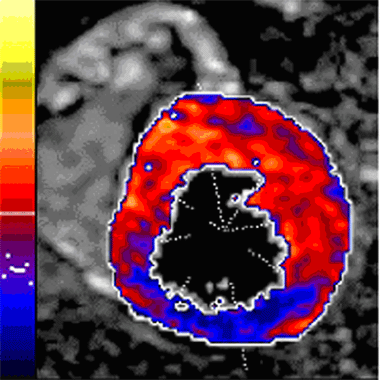

Zu Beginn der 90er Jahre erreichten die Magnet-Resonanz-Geräte einen Stand, der es erstmals erlaubte auch schnell bewegende Organe wie das Herz zu untersuchen [2,3]. Mit Geräten der Spitzenklasse können heute Herz-Untersuchungen mit höchster räumlicher Auflösung und entsprechender Detailinformation durchgeführt werden. Bei der Magnet-Resonanz-Technik wird die Bildinformation durch sich verändernde Magnetfelder erzeugt. Im Gegensatz zur Szintigraphie und Computer-Tomographie (CT) werden keine Röntgenstrahlen verwendet. Im Wissen um diese prinzipiellen Vorteile wurde die MR-Methode für die Messung der Herzmuskel-Durchblutung weiterentwickelt. Einige relevante kleine Studien auf diesem Gebiet [4] (siehe z. B. Abbildung 1) und auch die erste Multizenter-Studie, die die Einzel-Zenterresultate bestätigte, wurde von Zürich aus durchgeführt [5]. Basierend auf diesen Daten startete das MR-IMPACT-Programm (internationaler Vergleich zwischen der Herz-MR-Methode und der Herz-Szintigraphie). MR-IMPACT, der «Magnetic Resonance Imaging for Myocardial Perfusion Assessment in Coronary artery disease Trial» ist die bis anhin grösste multizentrische Herz-Szintigraphie-Studie [6]. Sie wurde am letztjährigen Kongress der Europäischen Gesellschaft für Kardiologie in Stockholm im Rahmen der «Clinical Trial Update Session» präsentiert und über einen Press-Release auch den Medien vorgestellt.

Abbildung 1: Die Herz-MR-Untersuchung weist eine Durchblutungsstörung der Hinterwand des Herzens nach (blauer Bereich; gut durchblutetes Herzmuskelgewebe: rot). In der anschliessenden Herzkatheter-Untersuchung konnte die eingeengte rechte Kranzarterie erfolgreich dilatiert und mit einem Stent versorgt werden. Die MR-Kontrolle zeigte wieder intakte Durchblutungsverhältnisse – ein drohender Infarkt konnte so